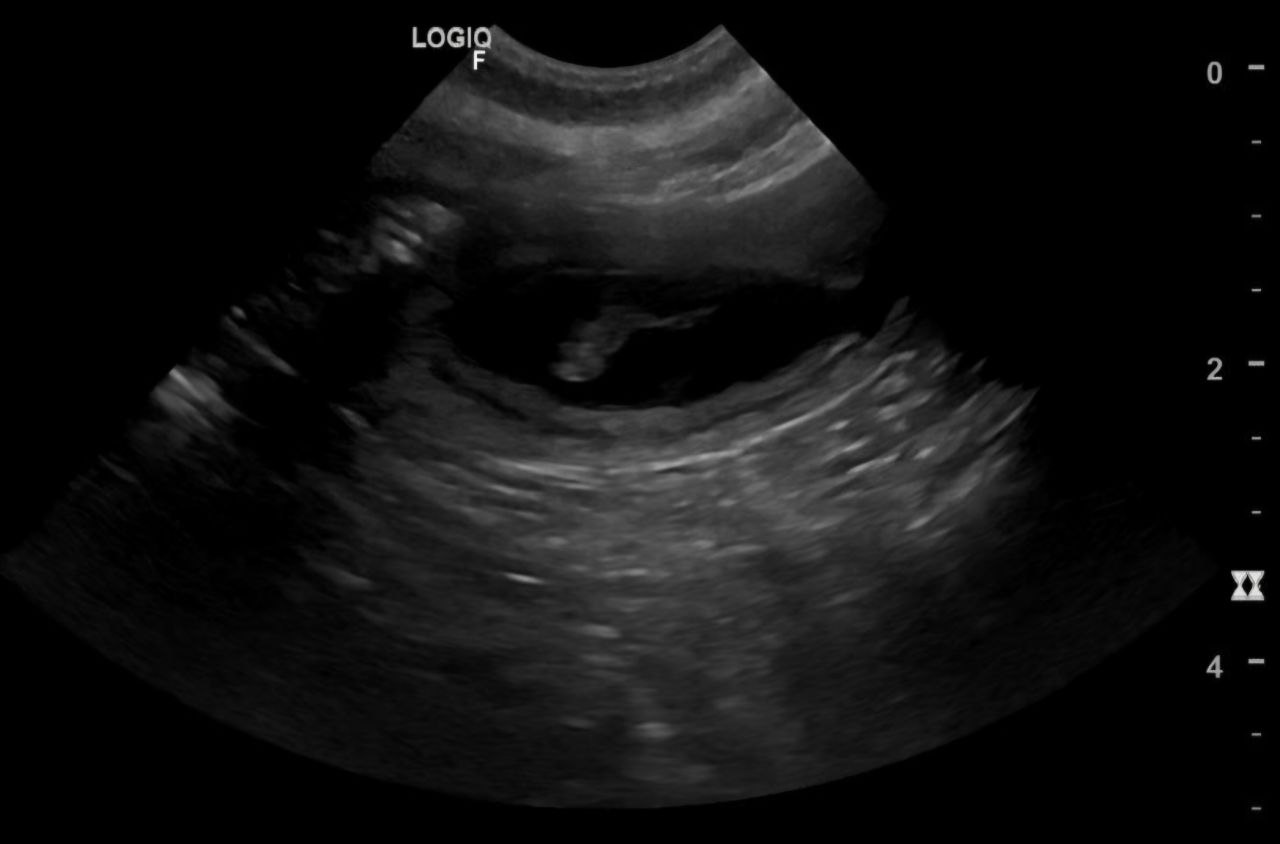

Am 10.12. hatten wir einen Ultraschall-Termin und die schon bereits vermutete Schwangerschaft wurde bestätigt.

Hier erkennt man schon einen Welpen.

Die Tierärztin konnte drei Welpen gleichzeitig im Ultraschall erkennen. Wie viele Welpen es aber genau sind, blieb bis zur Geburt eine Überraschung.